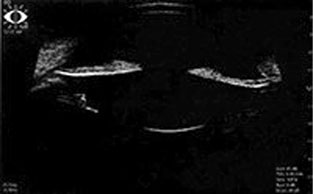

По данным ультразвуковой биомикроскопии переднего отрезка глаза (правый глаз — рис. 1, левый глаз — рис. 2), на обоих глазах отмечены выраженный пролапс радужки у корня, патологический контакт пигментного листка радужной оболочки с передней поверхностью хрусталика и цинновыми связками, размеры хрусталиков обоих глаз 3,62 мм, глубина передней камеры 3,96 мм.

Рис. 1. Правый глаз, исходная ультразвуковая биомикроскопия